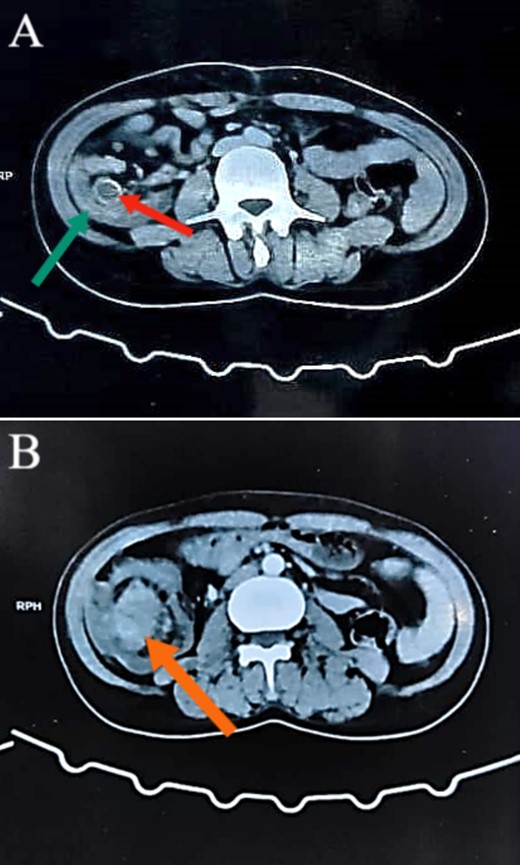

Colonoscopy revealed a malignant-looking mass, the mass appeared irregular, circumferential, fungating and was easily bleeding. It almost occluded the lumen, which correlated with the patient’s symptoms of chronic intermittent intestinal obstruction. The histopathology report indicated invasive moderately differentiated adenocarcinoma. An abdominal CT was conducted and reported a 7 × 5 cm2 soft tissue mass in the ascending colon, highly suspicious for colon cancer, with features of intussusception but no evidence of metastatic disease (Figs 1 and 2). Axial and coronal CT demonstrate the lesion and the intussuscepted bowel].

Abdominal CT images illustrating the presence of a concentric lesion in the cecum and proximal portion of the ascending colon, involving the terminal ileum. In (A), the red arrow indicates the terminal ileum within the cecal lumen, and the green arrow indicates the cecal wall (target sign). In (B), the orange arrow indicates the mass.